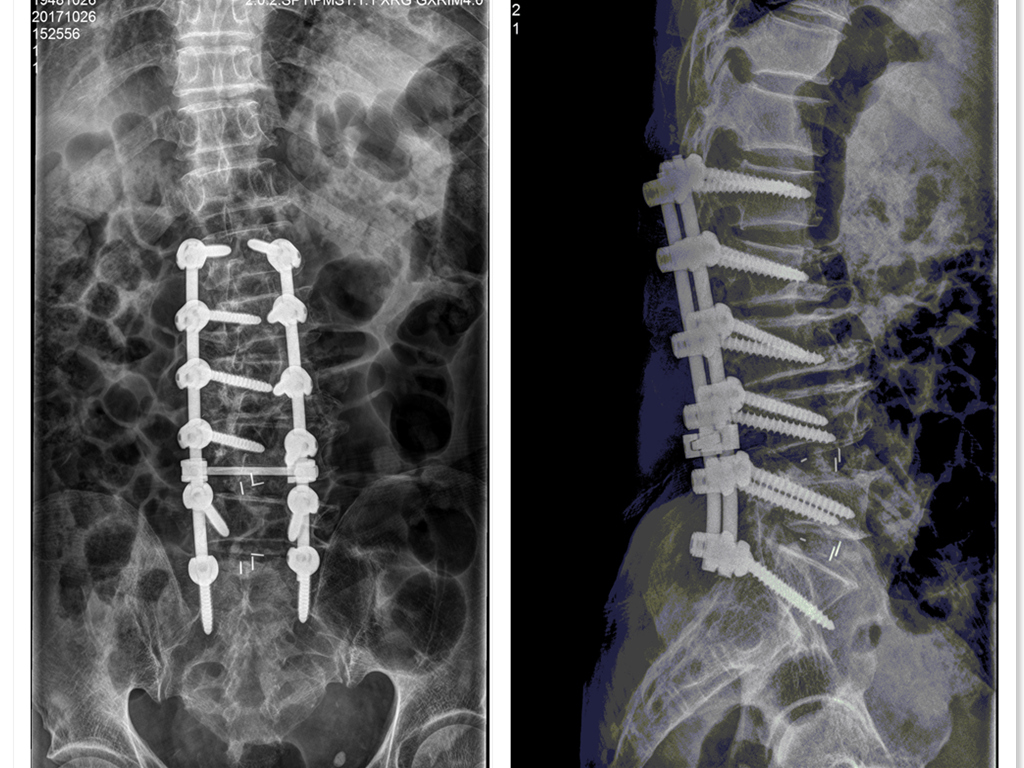

术后患者腰部及双侧下肢疼痛麻木消失,走路也不跛了,挺起了腰杆,家人竟然惊奇的发现他长高了3公分,邓大爷非常满意,笑着说:中医院医生的本事真大,不仅治好了腰痛,竟然还让我长高了,为庐江县中医医院骨伤科水平点赞。

其实邓老爷只是个例,我院骨伤二科在本地区甚至在周边地区颇有影响力,近年来,在退行性脊柱侧凸、颈椎病、腰椎滑脱症、腰椎间盘突出症、腰椎管狭窄症、胸腰椎骨折等脊柱方面疾病中医及手术治疗方面取得了良好的效果,多项技术填写本地空白,在县级医院处于先水平。